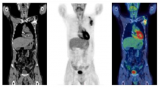

研究:FDG PET可能有助于肾上腺皮质癌的预后

来自波士顿哈佛大学的一组外科医生分析了被诊断为肾上腺皮质癌的患者在最初的FDG-PET扫描中肿瘤对放射性示踪剂的摄取。他们发现较高的最大标准化摄取值(SUVmax)与显著较差的存活率相关。 2022-10-09 PET/CT